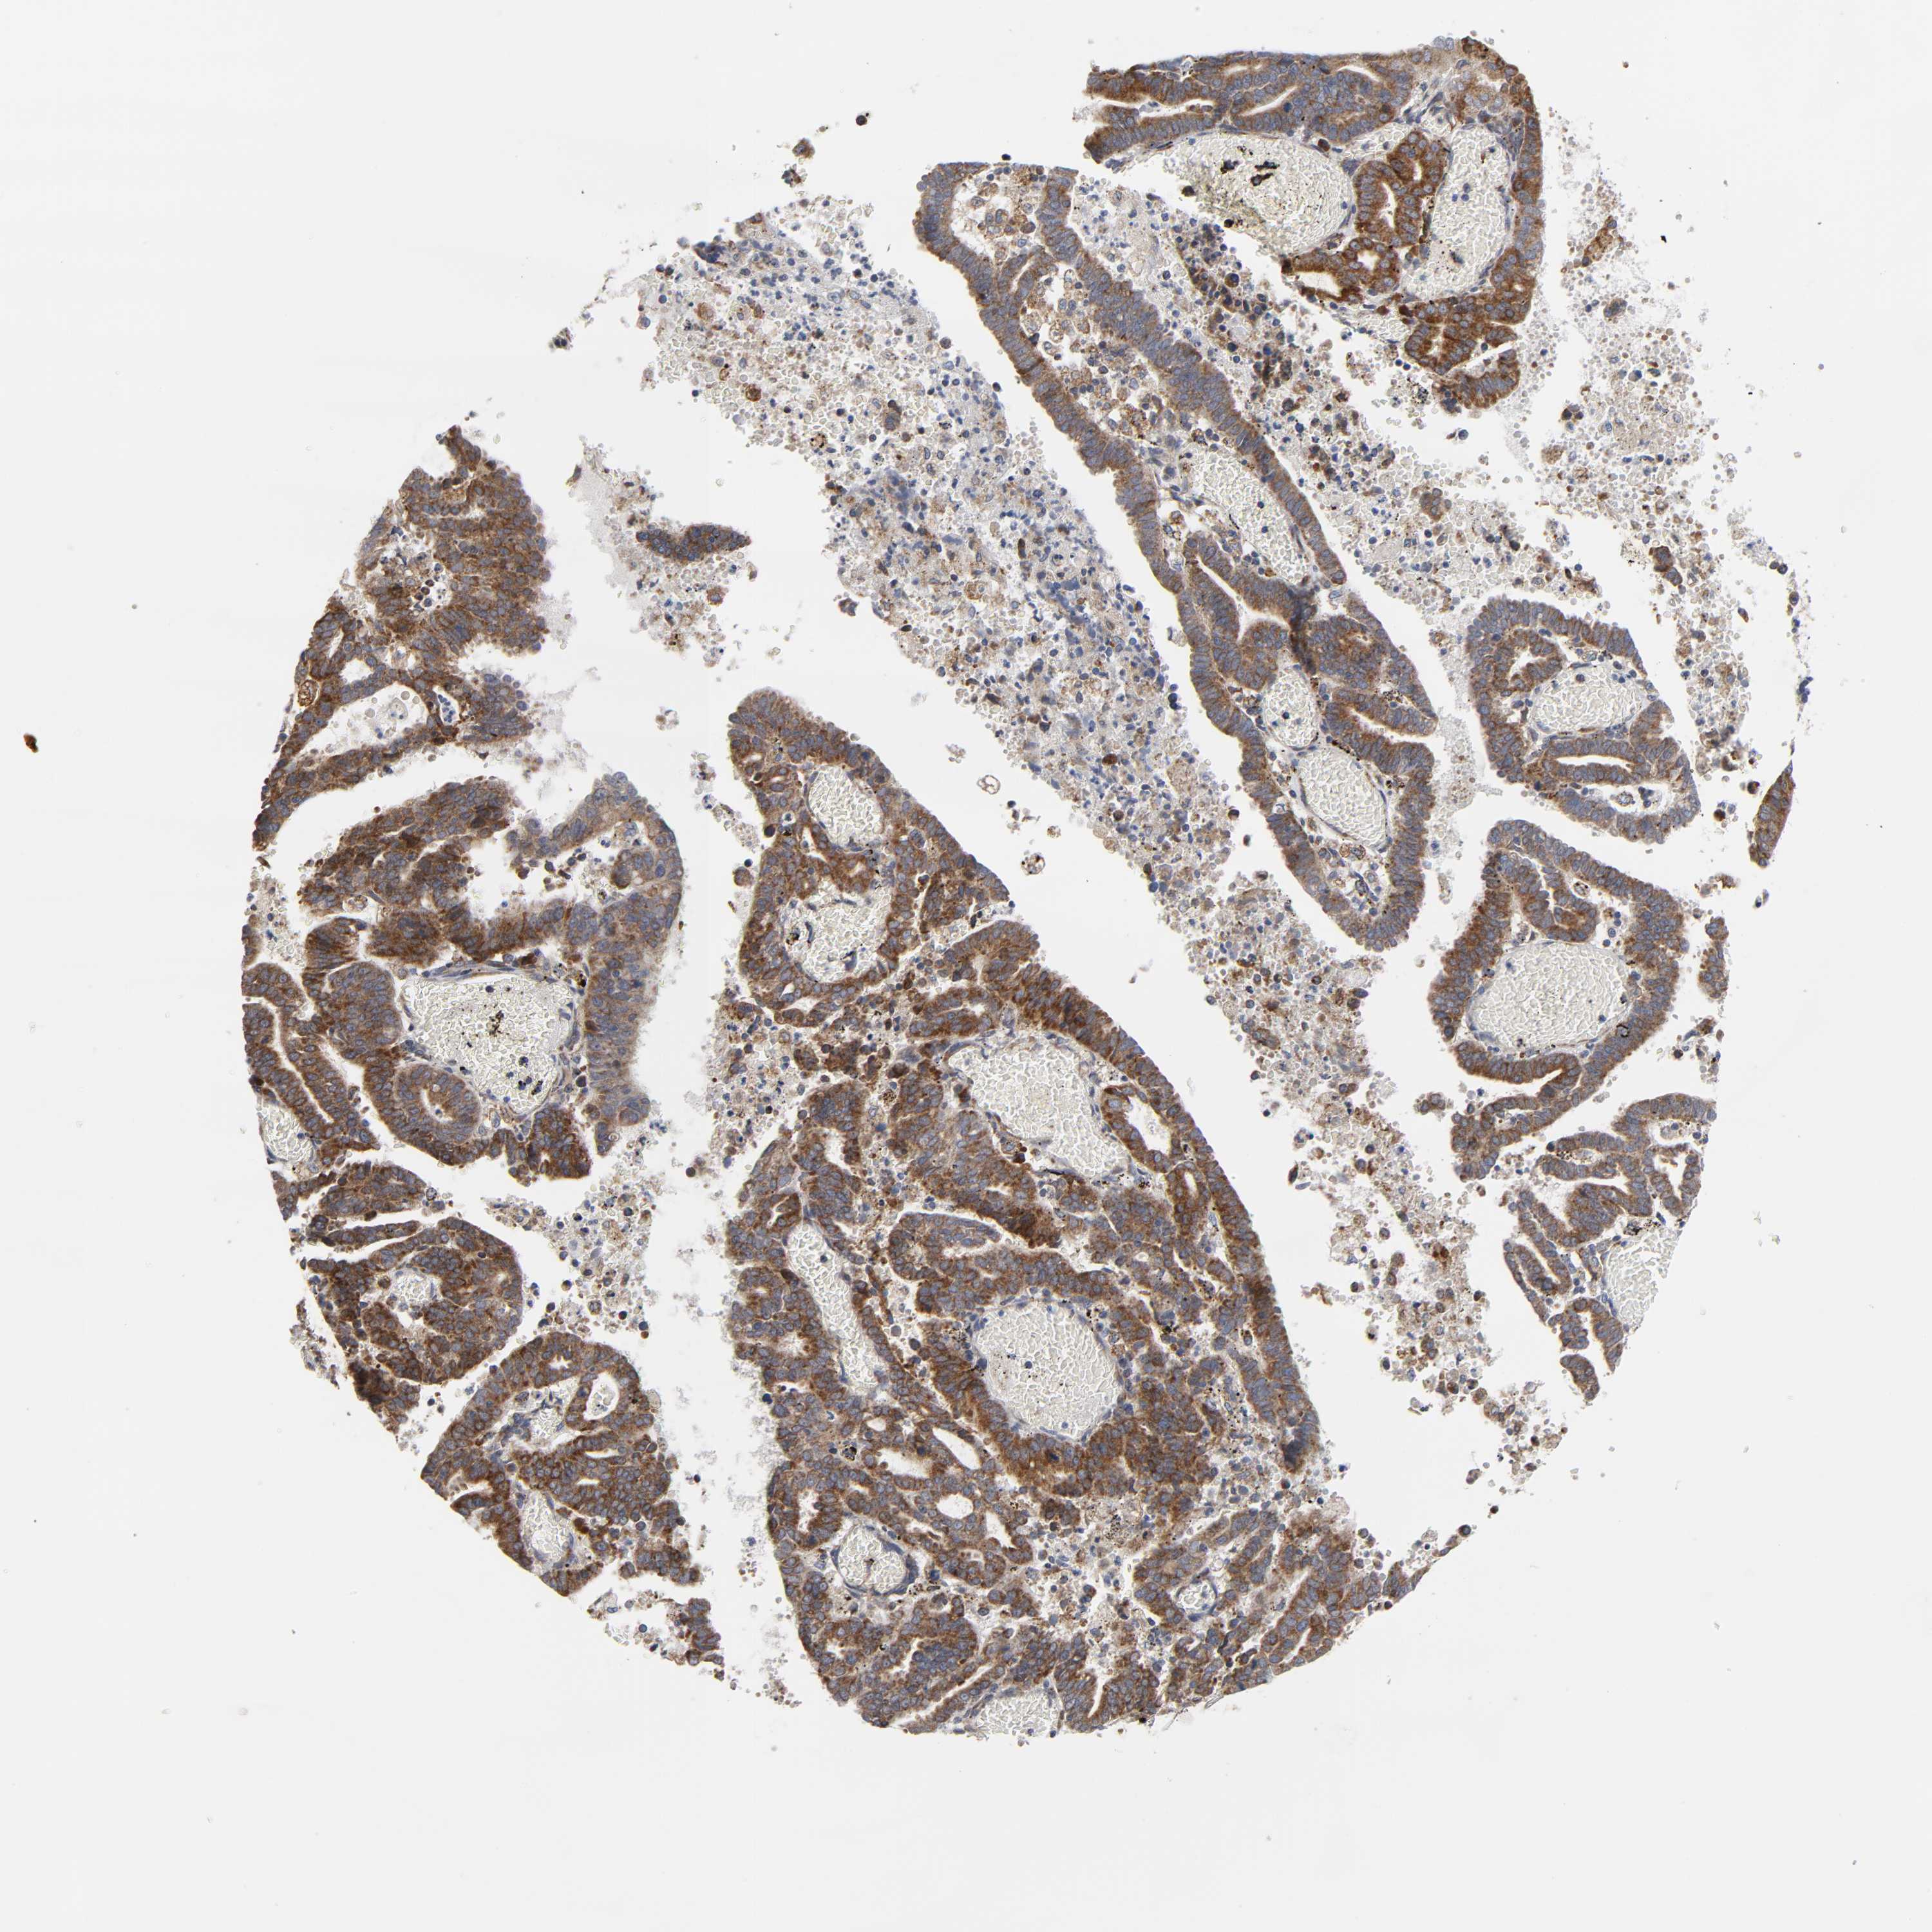

ENDOMETRIAL CANCER - Protein expressioni

A mouse-over function shows sample information and annotation data. Click on an image to view it in a full screen mode. Samples can be filtered based on level of antibody staining by selecting one or several of the following categories: high, medium, low and not detected. The assay and annotation is described here.

Note that samples used for immunohistochemistry by the Human Protein Atlas do not correspond to samples in the TCGA dataset.

Antibody stainingi

Antibody staining in the annotated cell types in the current human tissue is reported as not detected, low, medium, or high, based on conventional immunohistochemistry profiling in selected tissues. This score is based on the combination of the staining intensity and fraction of stained cells.

Each image is clickable and will lead to virtual microscopy that enables deeper exploration of all samples and also displays staining intensity scores, fraction scores and subcellular localization as well as patient and tissue information for each sample.

Antibody HPA027878

Antibody CAB004206

Staining

High

Medium

Low

Not detected

Intensity

Strong

Moderate

Weak

Negative

Quantity

>75%

75%-25%

<25%

None

Location

Nuclear

Cytoplasmic/membranous

Cytoplasmic/membranous,nuclear

Adenocarcinoma, NOS